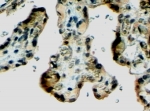

IHC staining of FFPE human placenta with Klotho antibody at 4ug/ml. HIER: steamed with pH6 citrate buffer, HRP-staining.